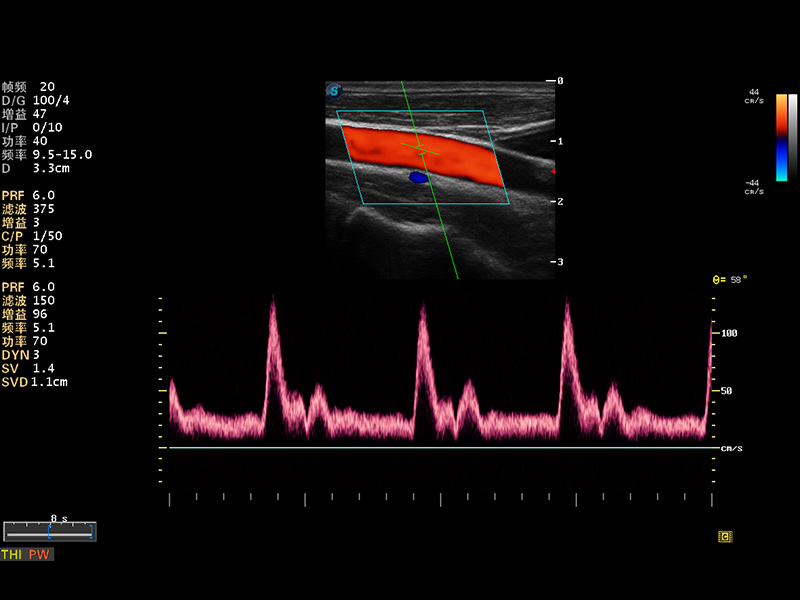

S8 EXP便携式彩色多普勒超声诊断仪是乐玩lewin国际研发的高端全身应用型便携彩超。高通道的VIS平台融合可视化(Visual)、智能化(Intelligent)和人性化(Smart)的特点,配以乐玩lewin国际自主研发生产的探头大家族,使您能够快速、准确的获得病人信息,提高工作效率的同时减轻疲劳。